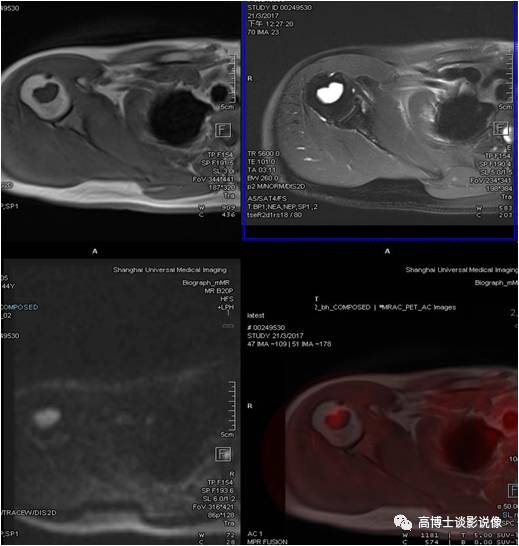

青年男性,右侧肱骨近端骨髓腔内类圆形异常信号灶,长径约2.6cm,FDG轻度摄取增高,考虑为内生软骨瘤。

点评

单发性内生性软骨瘤生长缓慢,病灶小,可长期无症状,注意避免剧烈外伤史,定期随访观察即可。